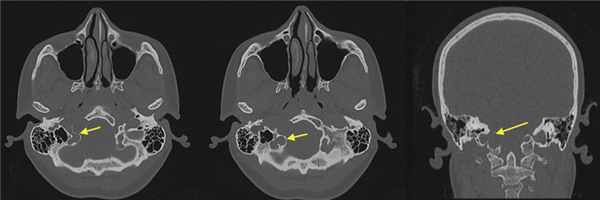

При СКТ головного мозга в костном режиме выявлен расширенный канал подъязычного нерва с деструкцией его стенок. Заднелатеральная стенка практически отсутствовала, вследствие чего полость канала сообщалась с просветом яремного отверстия (рис. 2). Рис. 2. СКТ головного мозга пациентки В. в костном режиме до операции. Определяется деструкция канала подъязычного нерва справа, канал отделен от полости яремного отверстия тонкой костной перегородкой (указано стрелкой).